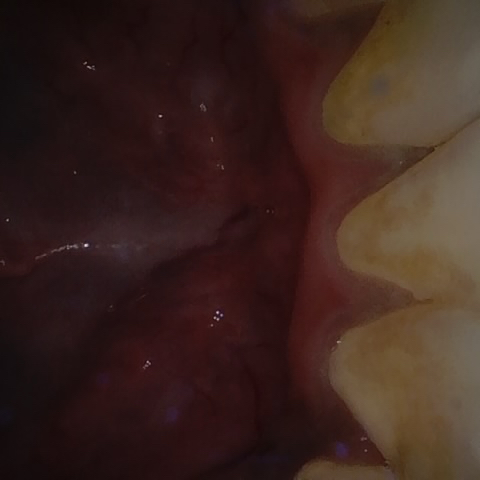

Annotated as "Good"